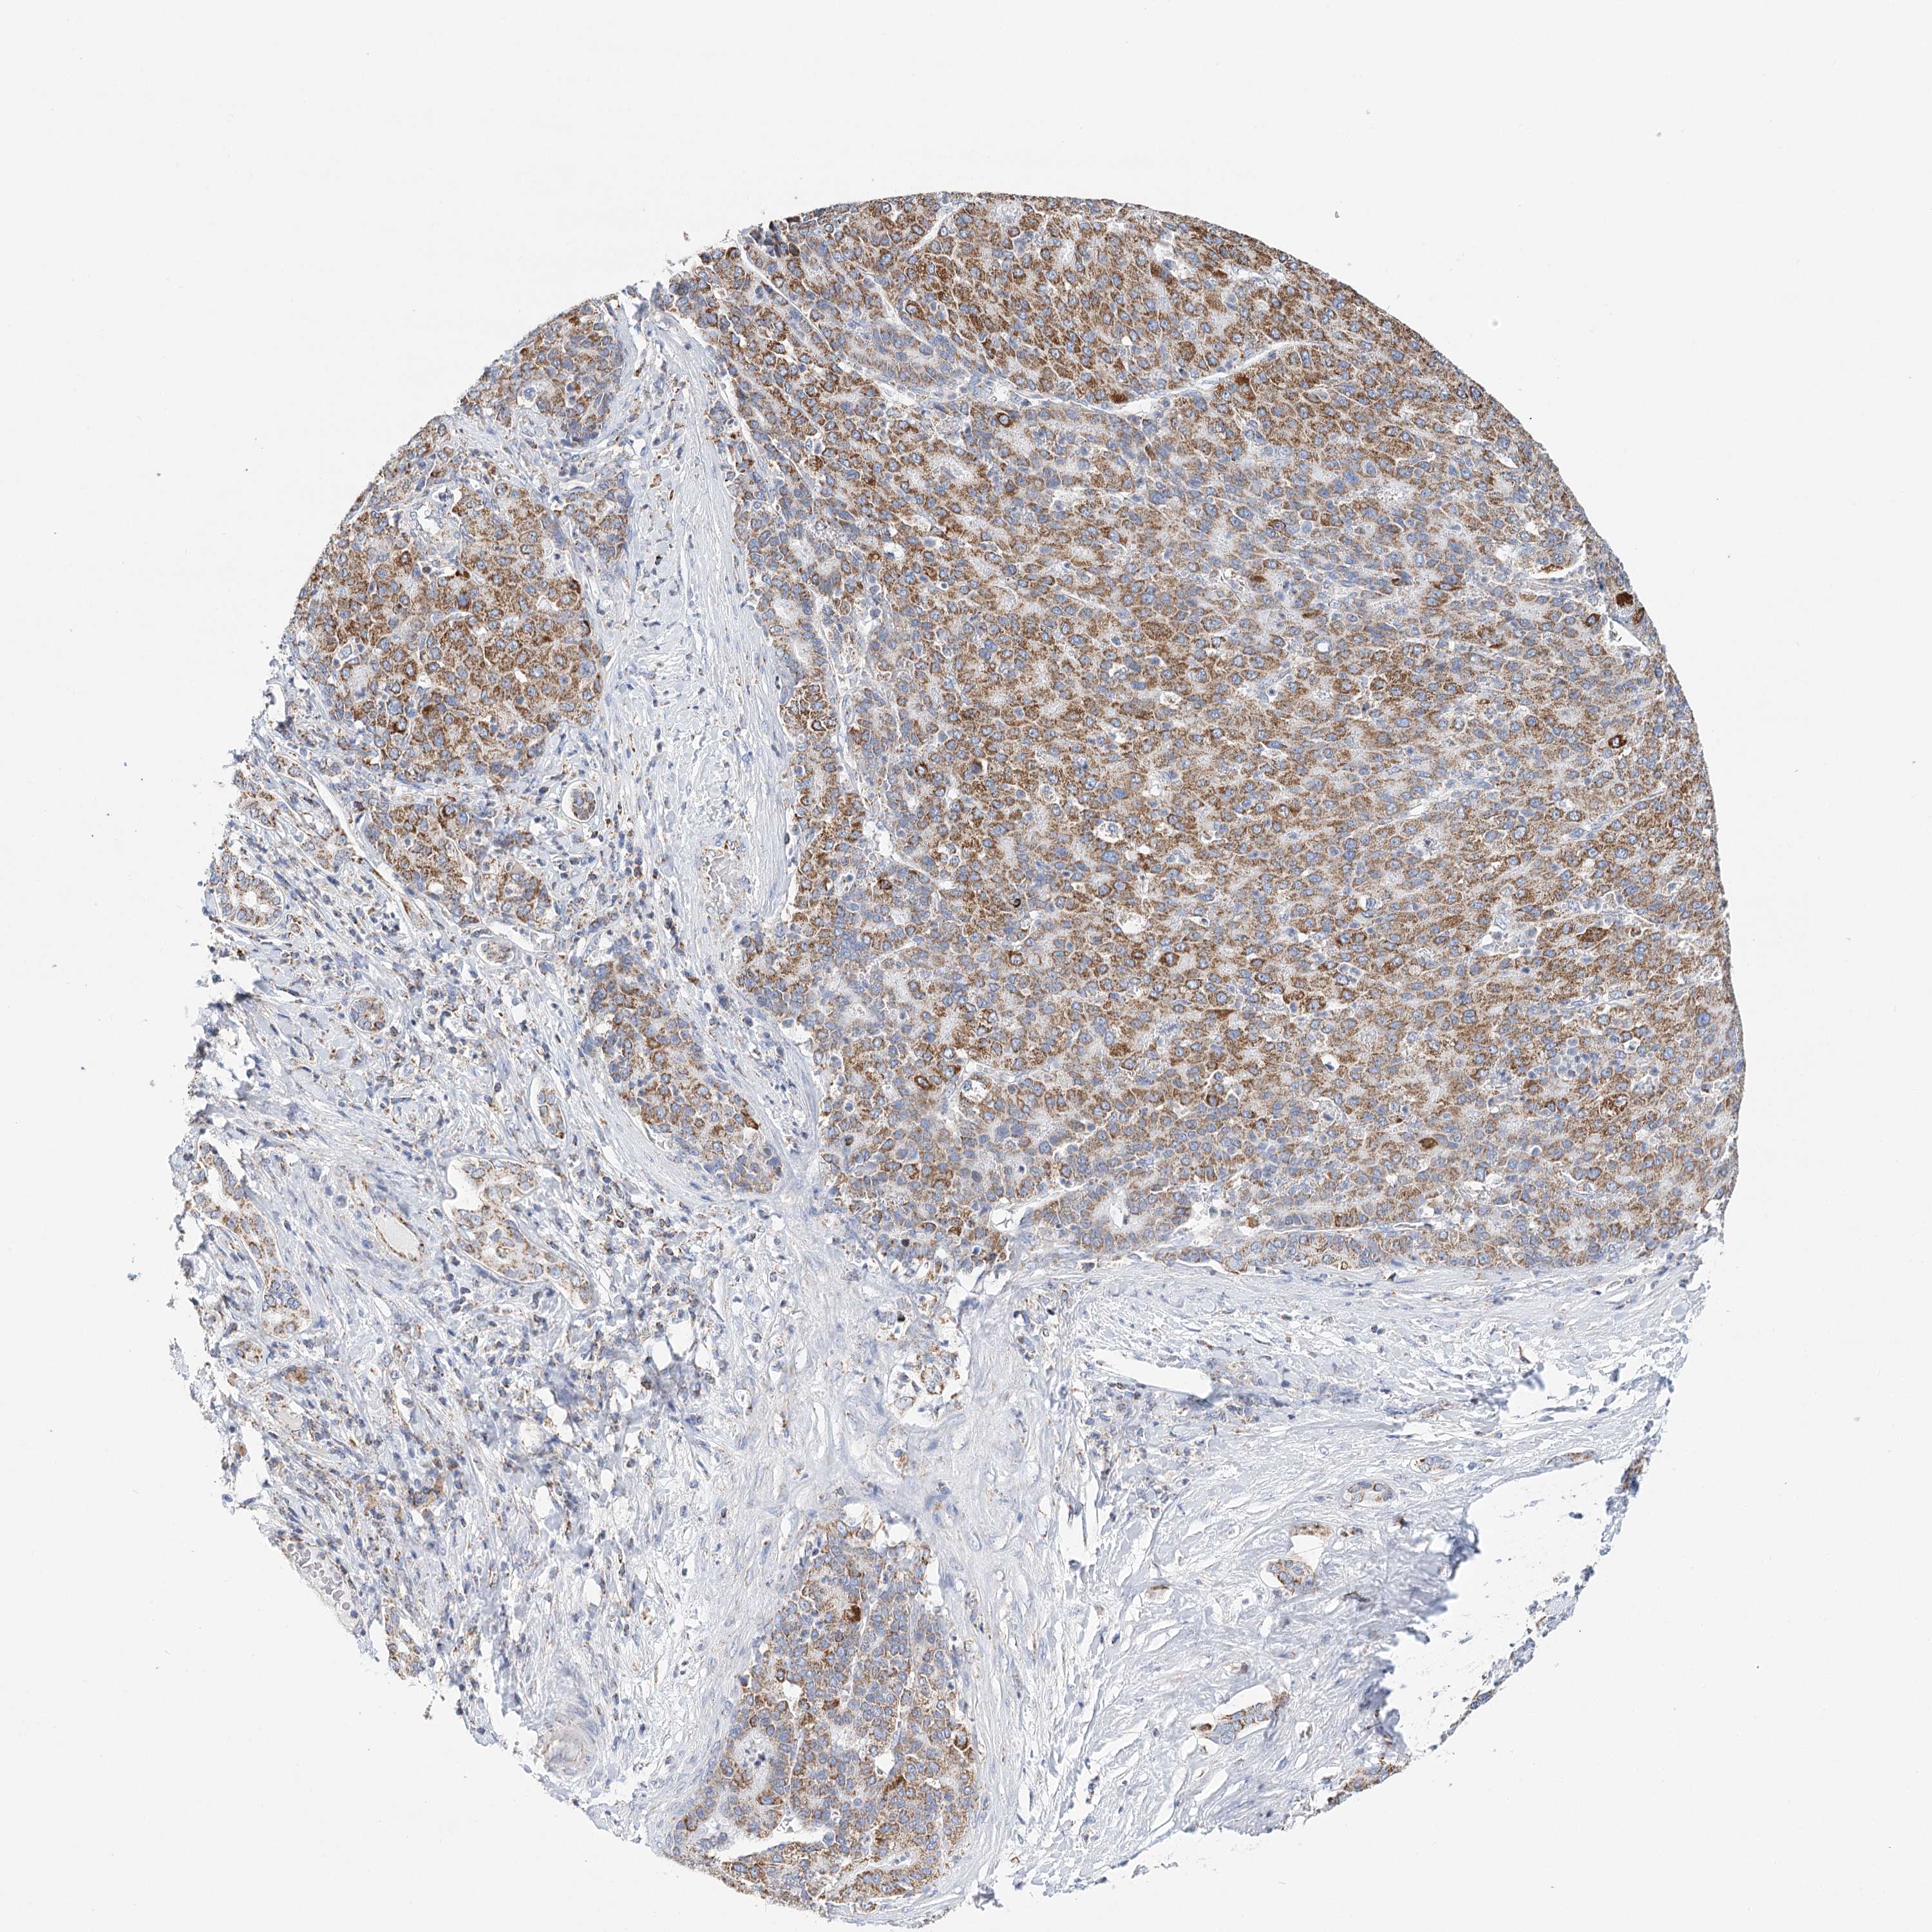

LIVER CANCER - Protein expressioni

A mouse-over function shows sample information and annotation data. Click on an image to view it in a full screen mode. Samples can be filtered based on level of antibody staining by selecting one or several of the following categories: high, medium, low and not detected. The assay and annotation is described here.

Note that samples used for immunohistochemistry by the Human Protein Atlas do not correspond to samples in the TCGA dataset.

Antibody stainingi

Antibody staining in the annotated cell types in the current human tissue is reported as not detected, low, medium, or high, based on conventional immunohistochemistry profiling in selected tissues. This score is based on the combination of the staining intensity and fraction of stained cells.

Each image is clickable and will lead to virtual microscopy that enables deeper exploration of all samples and also displays staining intensity scores, fraction scores and subcellular localization as well as patient and tissue information for each sample.

Antibody HPA032060

Antibody HPA032062

Antibody CAB034116

Staining

High

Medium

Low

Not detected

Intensity

Strong

Moderate

Weak

Negative

Quantity

>75%

75%-25%

<25%

None

Location

Nuclear

Cytoplasmic/membranous

Cytoplasmic/membranous,nuclear

Cholangiocarcinoma

Carcinoma, Hepatocellular, NOS